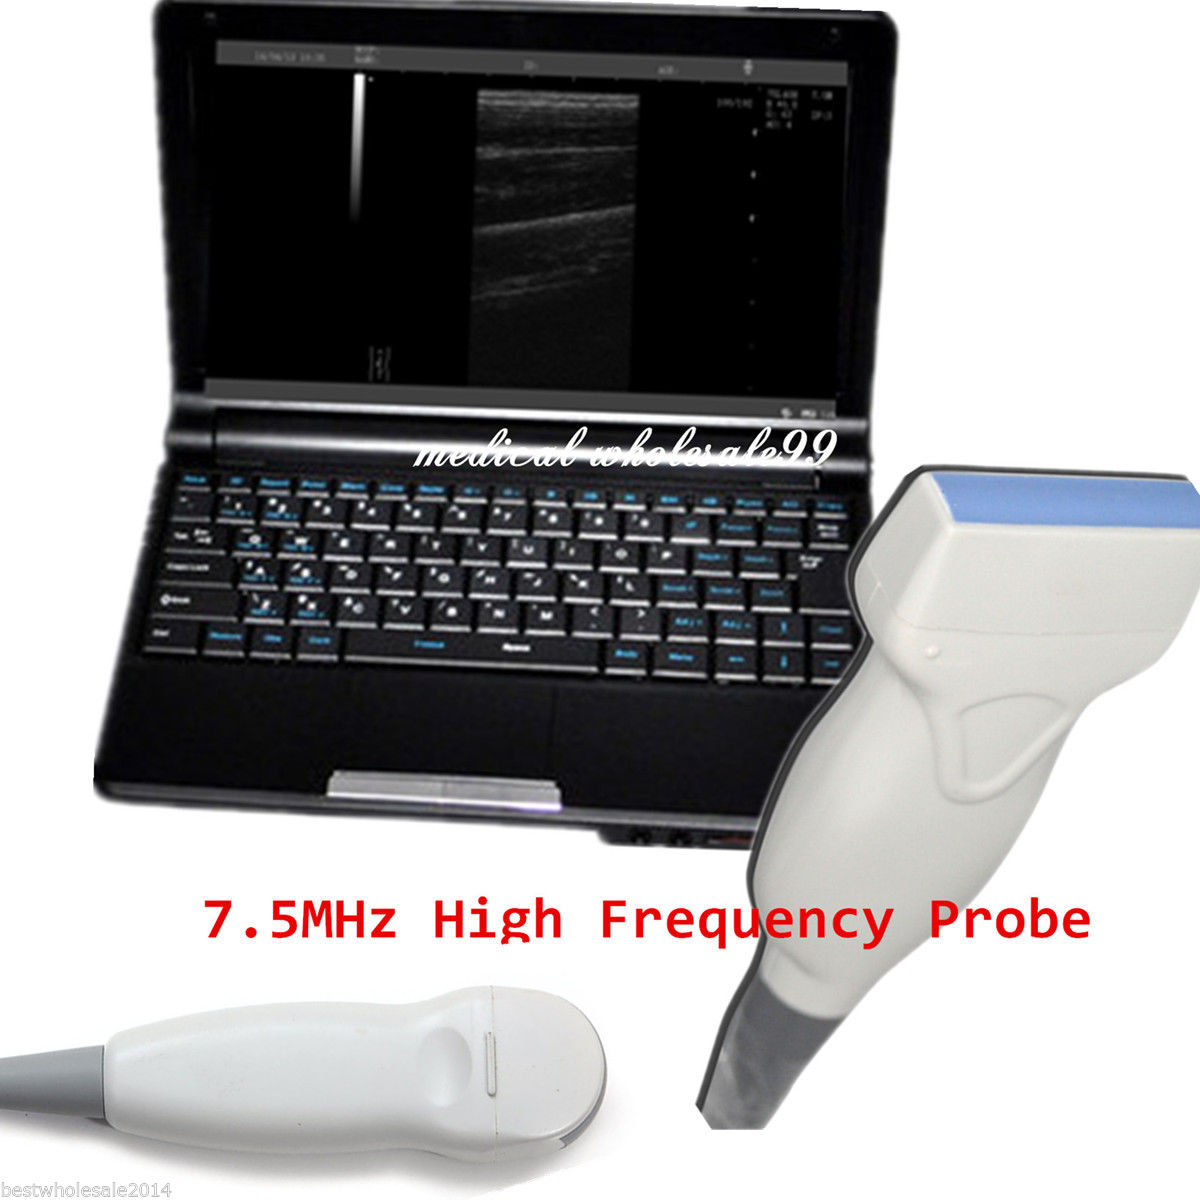

DIAGNOSTIC ULTRASOUND MACHINES FOR SALE

Laptop Ultrasound Scanner +Transvaginal Probes 3.5MHz Micro Convex Probes SALE !

Sale price$ 2,263.00

Regular price$ 2,414.00